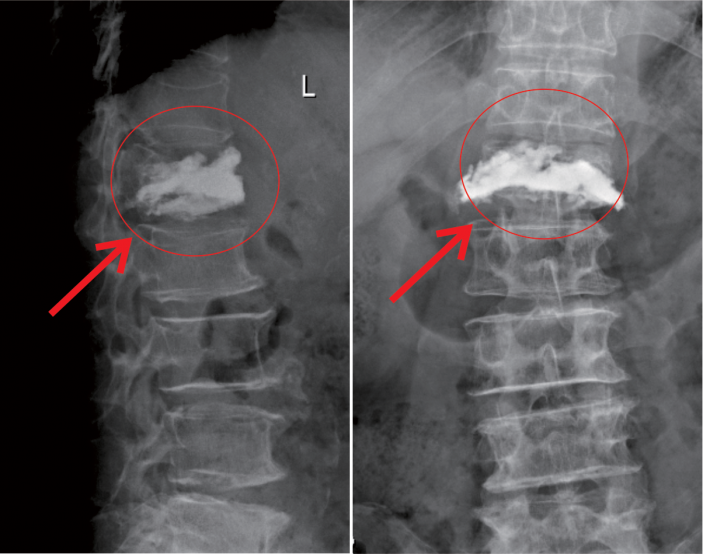

△術中注入骨水泥約11ml

在我院先進的術中三維CT引導下,杜教授确定L1雙側椎弓根進針點,娴熟地将穿刺針穿入L1椎體,經穿刺針建立通道将約11ml骨水泥注入坍塌的椎體中。術中監視,注入的骨水泥逐漸支撐起原本壓縮空洞的椎體。骨水泥凝固後,病變的椎體迅速恢複了承重能力。手術持續約40分鍾,開展非常成功,術後老人的疼痛馬上消失,翻身也無疼痛,第二天就能使用助步器下地行走。